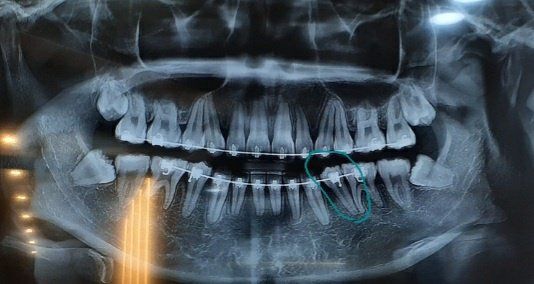

마무리 단계인데 저 쓰러진 치아를 세운다고 치축에 맞게 브라켓 각도를 바꾼다고 하셨는데용

현재로서는 단순히 일반철사, 고정식 철사만으로는 치열이 많이 틀어질지 모릅니다. 또한 파노라마 사진 자료를 통해서는 알 수 없으며 ceph.자료 및 임상사진 등 여러가지 자료를 종합적으로 판단해야 합니다. 파노라마 사진은 3차원적인 자료를 2차원적으로 표현했기 때문에 왜곡이 심합니다. 따라서 지금으로서는 판단하기 힘듭니다.

교정은 거의 끝나신거 같으시고, 표시된치아의 치아 장축을 바꾼다는거니 치열에 크게 영향을 미칠건같지 않습니다. 오랜기간동안 고생하셧으니 끝까지 믿고 교정마무리 잘하시면되실꺼 같아요.